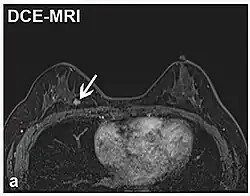

| Realce de contraste dinâmico | DCE | Medidas de mudanças ao longo do tempo no encurtamento da relaxação spin-lattice (T1) induzido por um bolo de contraste de gadolínio.[85] | O aumento rápido do contraste de gadolínio, juntamente com outras características, sugere malignidade.[86] |  | |